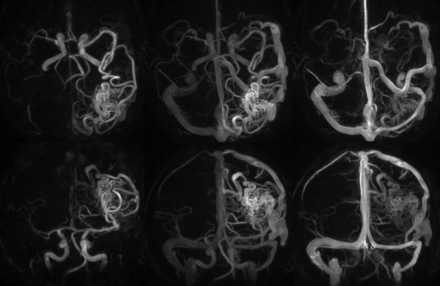

HYPRFlow images of a left parietal occipital AVM, demonstrating whole-brain coverage and isotropic 0.68-mm resolution. Top row: axial HYPRFlow MIP images left to right: arterial, mixed, and venous phase. Bottom row: the same image data projected into the coronal plane, left to right: arterial, mixed, and venous phase images.